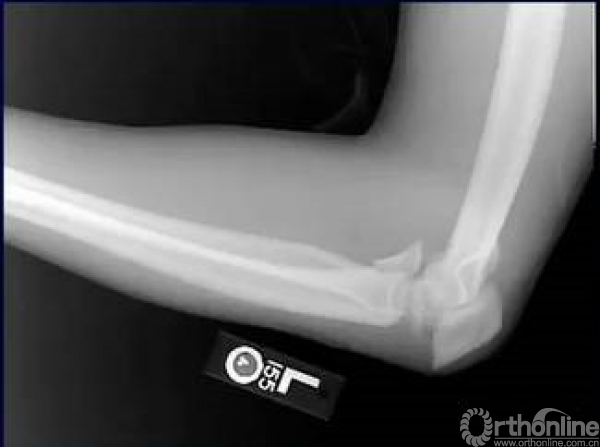

今天小编跟大家探讨一下尺骨鹰嘴骨折和张力带,鹰嘴骨折十分常见,经常还伴随着肘关节脱位colton分型。

目前的主要治疗方法则分为钢板固定和张力带固定。